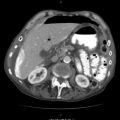

Fig. 17.1

Probe positions for FAST